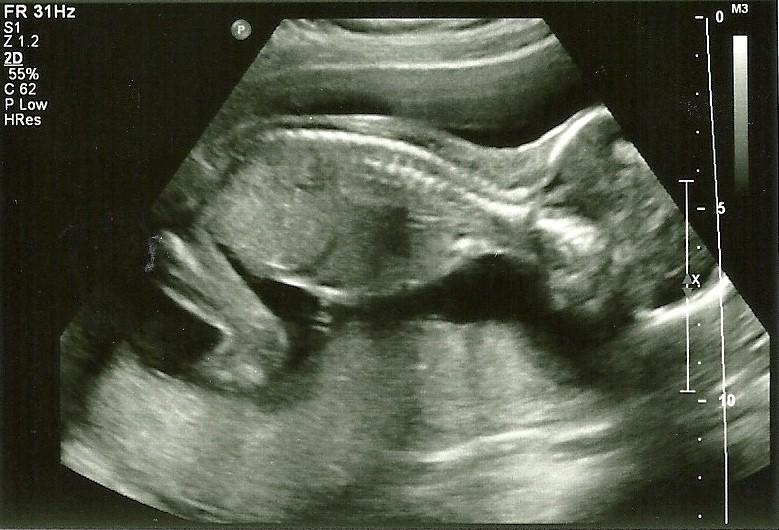

| Echo gemaakt op 2 januari 2013. Hier is 30 weken en al zo groot dat ze niet helemaal meer in beeld past. |